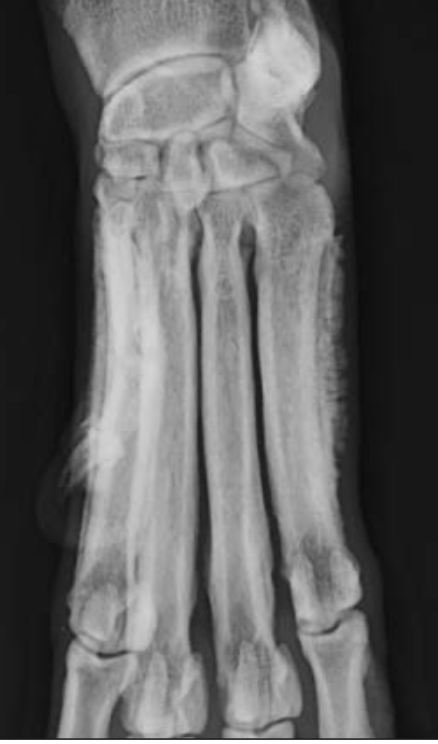

Which type of lysis is affecting the distal 4th metatarsal bone?

A

Geographic; note the cortical thinning and expansion.